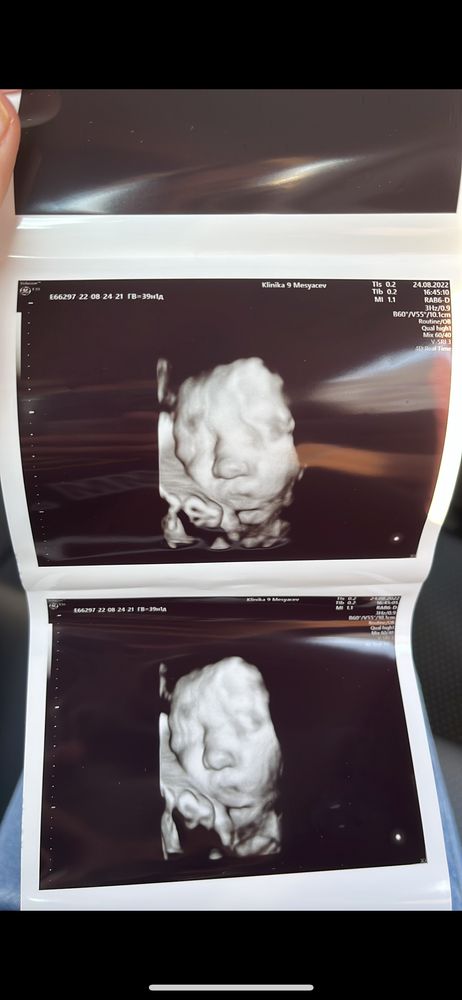

Изображение Изображение Изображение

Александра, там на фото написаны сроки, 2 фото - 37н 1, 3 фото - 39н 1 На первом фото к сожалению нет информации, но думаю месяц 3-4

Мне на втором скрининге включили 3д режим, сделали фотографии. А на третьем скрининге малышка уже упёрлась лицом в матку, и красивых фоток не получилось 🥲